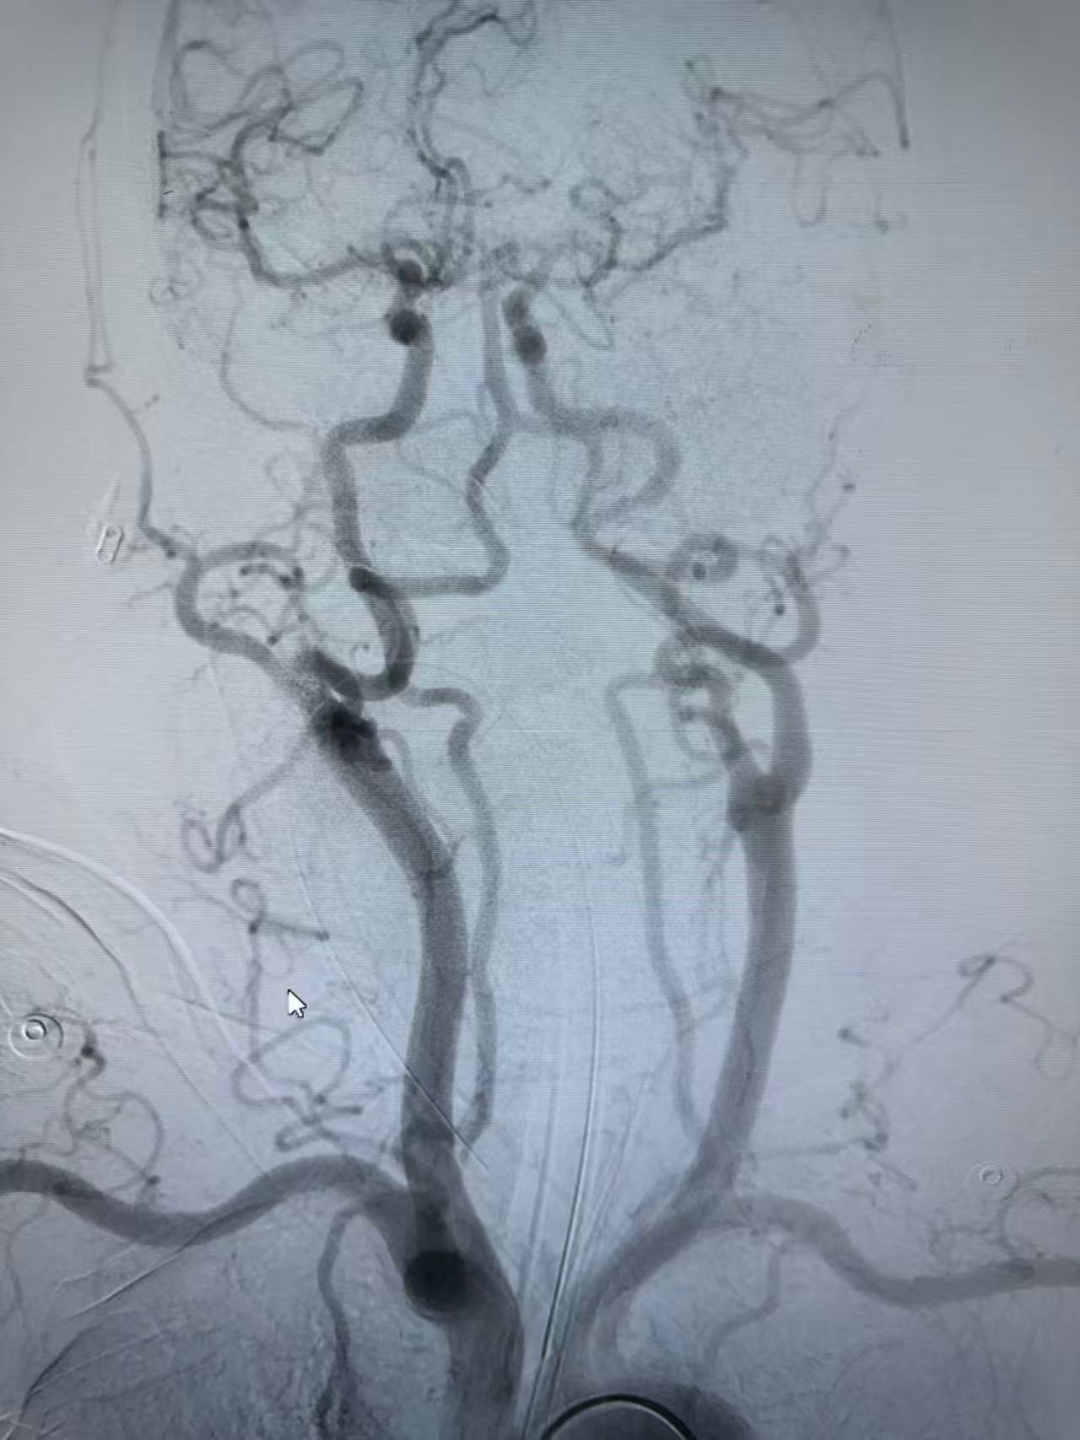

弓上造影:II型弓,大脑中动脉栓塞。

确认血栓完全取出后,球囊泄压,术后即刻造影显示大脑中动脉闭塞再通, mTICI评分3级。

无明显造影剂渗漏及脑梗死表现。